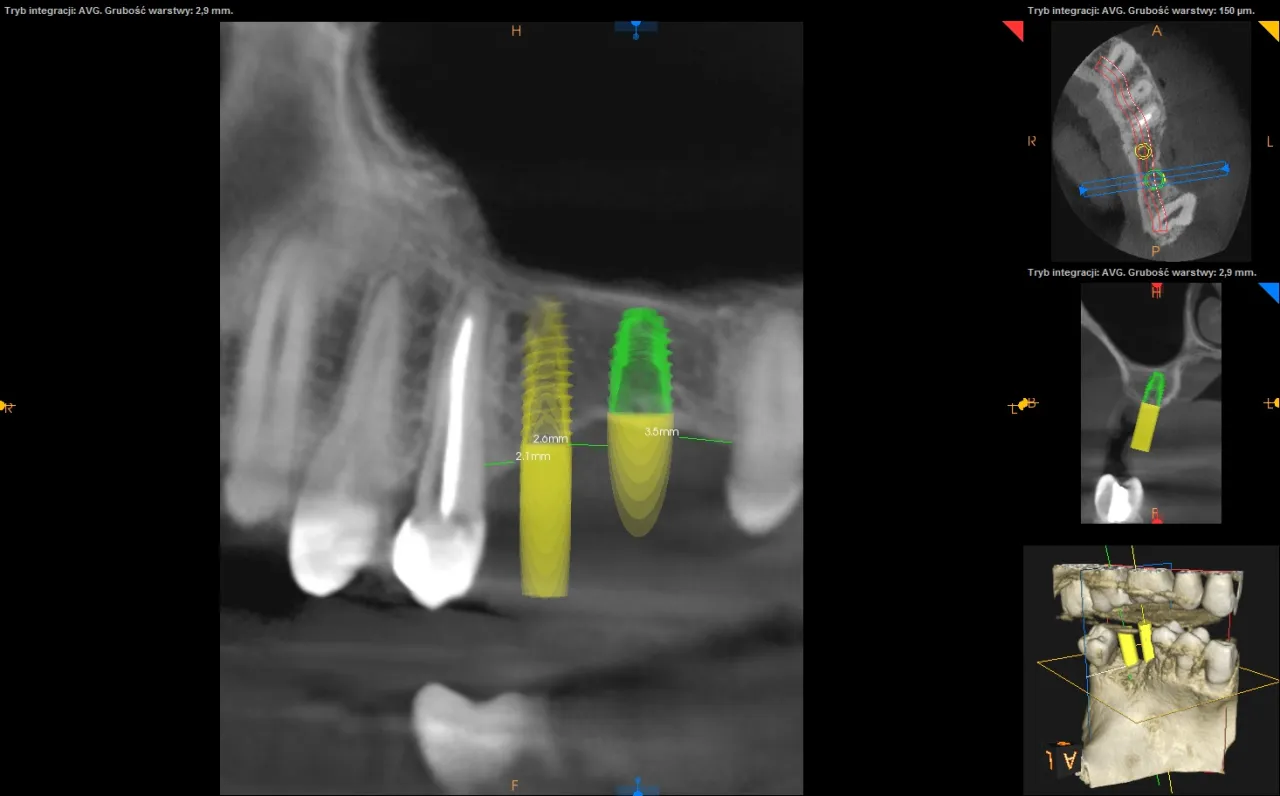

Absolutnie niezbędnym elementem diagnostyki przed wszczepieniem implantu jest tomografia komputerowa (CBCT). To nie jest zwykłe zdjęcie rentgenowskie; CBCT dostarcza trójwymiarowy obraz Twoich struktur kostnych. Dzięki niej mogę precyzyjnie ocenić ilość i jakość kości w miejscu planowanego implantu, a także zidentyfikować ważne struktury anatomiczne, takie jak nerwy czy zatoki szczękowe. To pozwala mi na bezpieczne i precyzyjne zaplanowanie pozycji implantu, minimalizując ryzyko powikłań i zapewniając długotrwały sukces.

Współczesna stomatologia to w dużej mierze technologia cyfrowa. Na podstawie danych z tomografii CBCT przeprowadzam wirtualne planowanie leczenia. Oznacza to, że na ekranie komputera projektuję optymalną pozycję implantu, uwzględniając wszystkie aspekty od ilości kości, przez sąsiednie zęby, aż po przyszłą koronę. Następnie, na podstawie tego wirtualnego projektu, tworzymy indywidualny szablon chirurgiczny, który jest drukowany w 3D. Ten szablon to moje "GPS" podczas zabiegu prowadzi wiertło z niezwykłą precyzją, co zwiększa bezpieczeństwo, minimalizuje inwazyjność i skraca czas zabiegu.